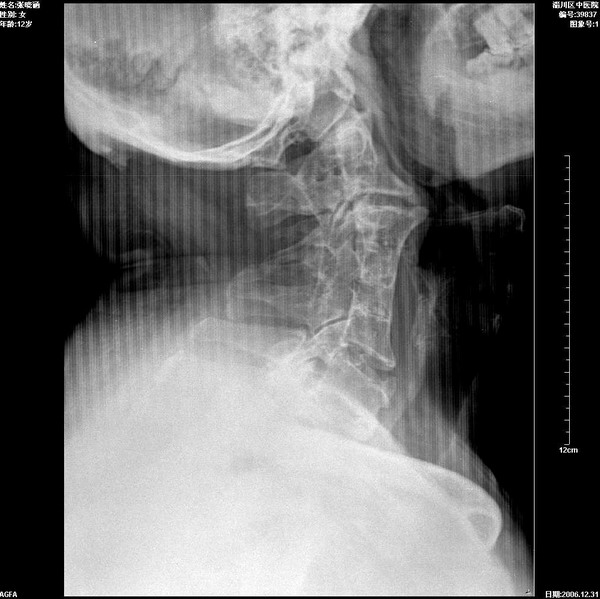

典型罕见病例    患者男35岁,颈部不适

环椎枕化,c3、4、5、6融椎畸形,建议察看有无其它异常,以除外klppel-fell综合征

典型!!环椎枕化,多节融椎畸形。